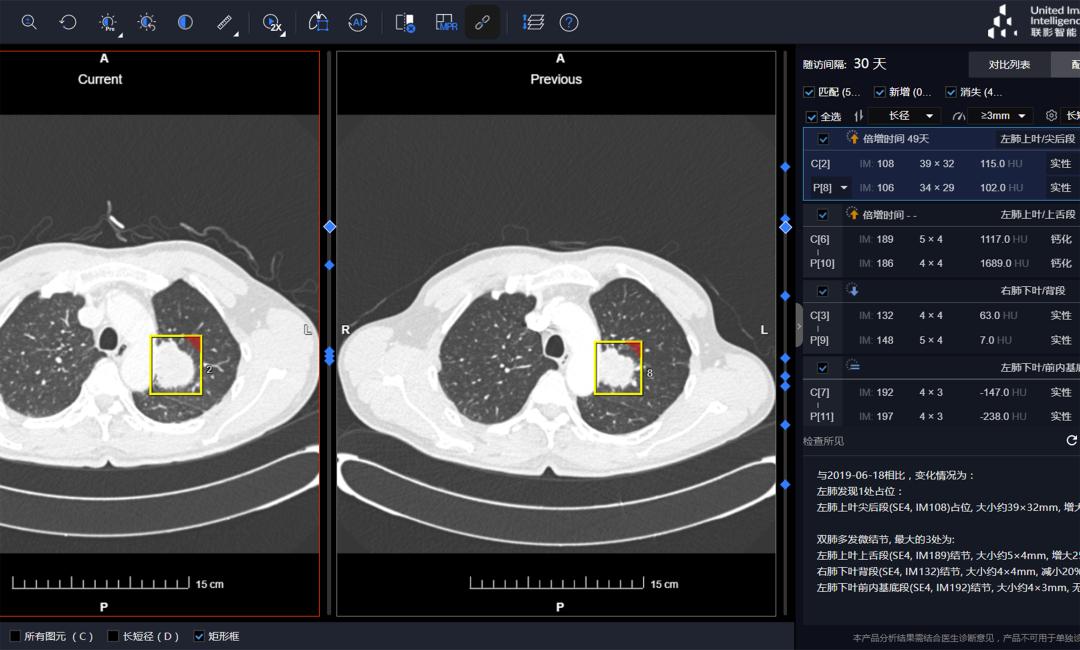

此外,人工智能在肺部病变的临床诊断的应用已落地且越来越成熟。

在中国临床AI肺结节诊断系统有三家公司获批:深睿医疗、推想科技、联影智能。